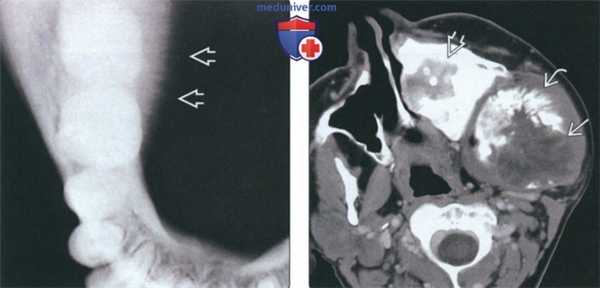

(Слева) На окклюзионной рентгенограмме нижней челюсти справа определяется лучистая периостальная реакция со стороны язычной поверхности - типичный признак остеосаркомы, который можно обнаружить и при других злокачеавенных опухолях.

(Справа) На аксиальной КТ с КУ определяется вновь возникшая оаеосаркома нижней челюсти у пациента, получавшего лечение по поводу фиброзной дисплазии верхней и нижней челюаи. Обратите внимание на экспансивную деструктивную опухоль с классической периостальной реакцией выделяющуюся на фоне диффузного утолщения верхней челюсти, обусловленного фиброзной дисплазией.1. Общая характеристика: